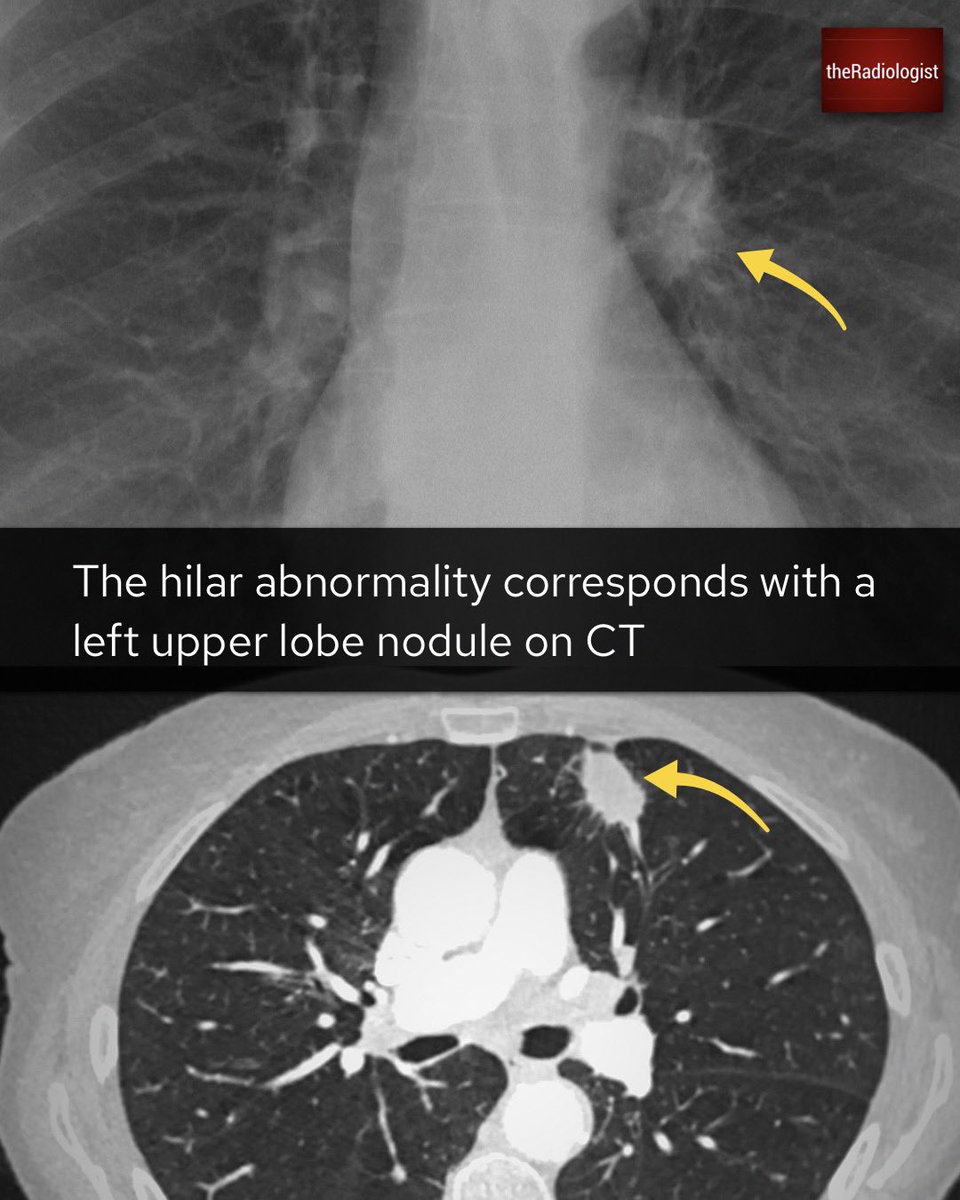

Explanation 2/3

Explanation 3/3